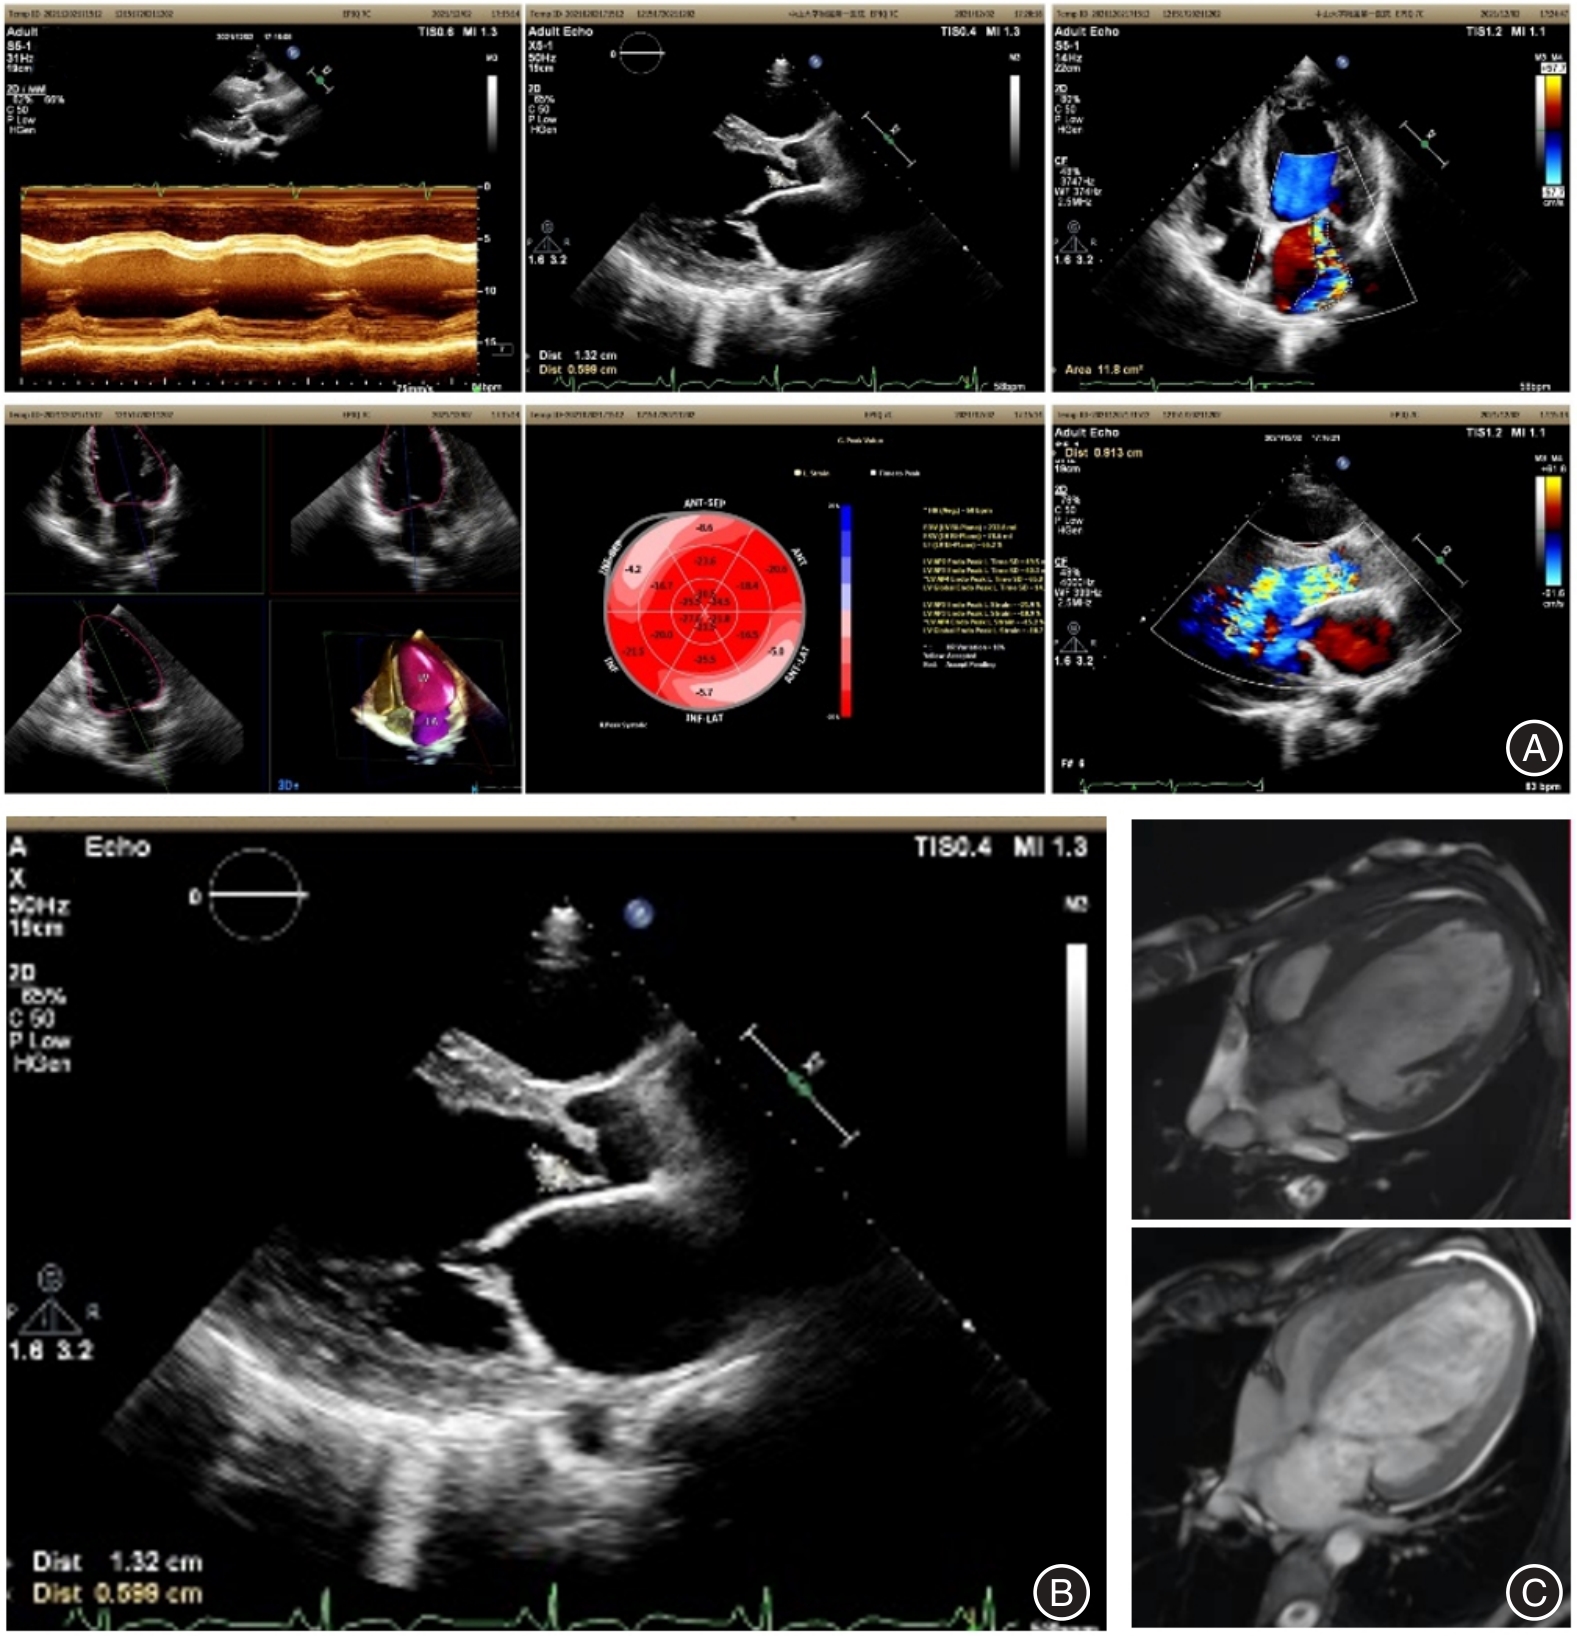

1例36岁青年男性因胸闷、气促10余天入院,超声心动图提示主动脉瓣重度关闭不全、主动脉瓣赘生物、二尖瓣重度关闭不全、左房左室增大。经多学科会诊讨论,以患者主动脉瓣赘生物为切入点,将患者瓣膜病病因聚焦在血培养阴性的感染性心内膜炎(IE)和非细菌性血栓性心内膜炎,并与风湿性心脏瓣膜病相鉴别。最终经外科主动脉瓣置换术取赘生物行组织病理学、生物培养及病原微生物高通量宏基因组二代测序,最终确诊为贝纳特柯克斯体导致的主动脉瓣感染性心内膜炎(Q热IE)。

A 36-year-old male patient was hospitalized due to persistent chest tightness and dyspnea lasting over 10 days. An echocardiogram revealed significant aortic valve regurgitation, the presence of vegetation on the aortic valve, severe mitral valve regurgitation, and enlargement of both the left atrium and left ventricle. Following a comprehensive multidisciplinary consultation, the focus was directed towards the aortic valve vegetation as the primary concern, with particular attention given to the potential diagnosis of blood culture-negative infective endocarditis (IE) and non-bacterial thrombotic endocarditis, while differentiating it from rheumatic heart disease. Ultimately, the vegetation was excised during a surgical aortic valve replacement procedure, which facilitated histopathological examination, biological culture, and high-throughput metagenomic sequencing of pathogenic microorganisms. The definitive diagnosis was established as aortic valve infective endocarditis (Q fever IE) leading by infection of Coxiella burnetii.